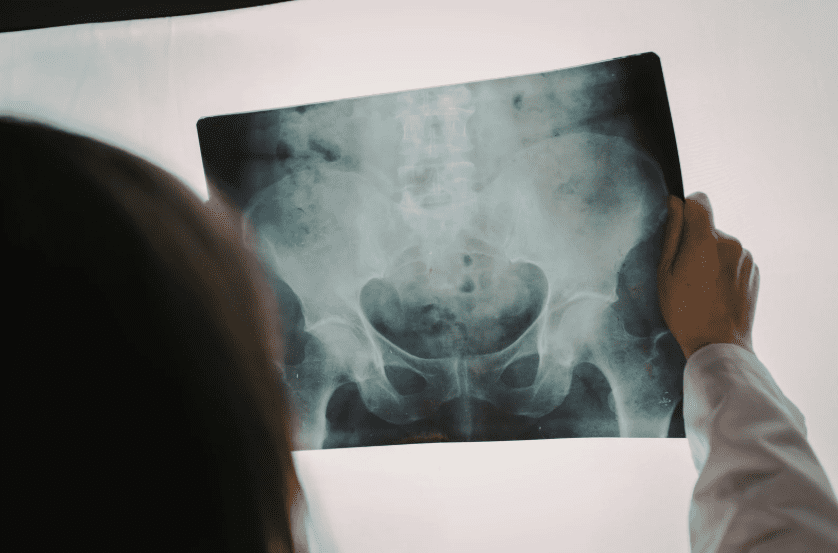

Die moderne Radiologie stützt sich auf mehrere Bildgebungstechniken, die jeweils für spezifische diagnostische Zwecke entwickelt wurden. Röntgenaufnahmen sind eine der am häufigsten verwendeten Methoden und werden häufig zur Untersuchung von Knochen, Gelenken und der Brust durchgeführt. Sie liefern schnelle Ergebnisse und sind oft der erste Schritt bei der Bewertung von Frakturen, Lungenerkrankungen oder Ausrichtungsproblemen.

Die Computertomographie, allgemein bekannt als CT, kombiniert mehrere Röntgenbilder, um detaillierte Querschnittsansichten des Körpers zu erstellen. Diese Technik ermöglicht es Ärzten, Organe, Blutgefäße und Gewebe mit größerer Klarheit zu untersuchen. CT-Scans werden häufig in Notfallsituationen, zur Beurteilung von Verletzungen und zur Bewertung komplexer innerer Zustände eingesetzt.

Die Magnetresonanztomographie oder MRT verwendet Magnetfelder und Radiowellen anstelle von Strahlung. Sie ist besonders effektiv zur Darstellung von Weichteilen wie Muskeln, Bändern, Gehirn, Rückenmark und inneren Organen. MRT wird oft gewählt, wenn detaillierte Bilder benötigt werden, ohne Patienten Strahlung auszusetzen.

Neben diesen Methoden bieten spezialisierte Bildgebungstechniken wie 3D-Mammographie fortschrittliches Screening für spezifische gesundheitliche Probleme. Jede Bildgebungstechnik erfüllt einen einzigartigen Zweck, und Ärzte wählen sorgfältig die am besten geeignete Option basierend auf Symptomen, Krankengeschichte und diagnostischen Zielen aus.